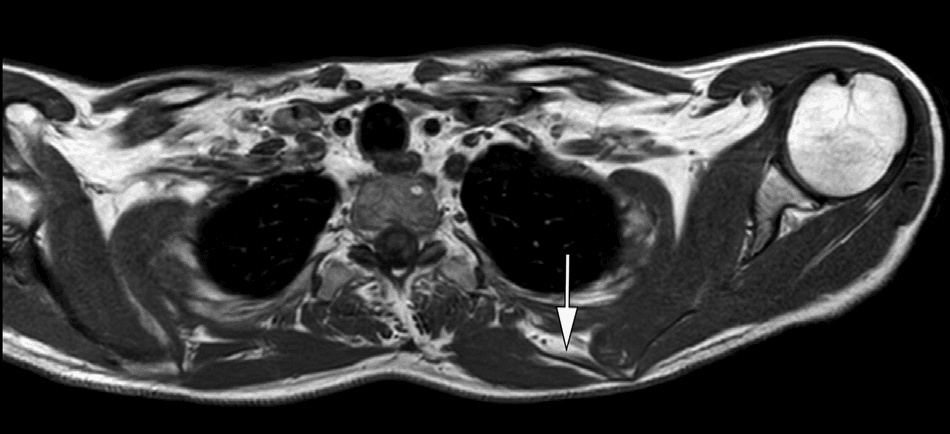

Figure 2. 좌측 대능형근(major rhomboid muscle)의 위축을 보여주는 자기공명영상(MRI) T1 강조 축상면 영상입니다. 영상에서 좌측 대능형근의 근위축이 명확하게 관찰되며, 이는 배측견갑신경병증으로 인한 신경지배 근육의 변성을 의미합니다. MRI를 통한 근위축의 확인은 배측견갑신경병증의 진단과 중증도 평가에 중요한 영상학적 근거를 제공합니다.